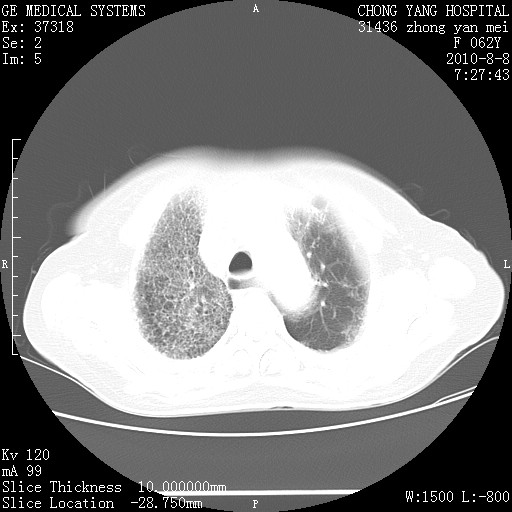

标题: CT28269:F62Y咳嗽胸痛数月。 [打印本页]

标题: CT28269:F62Y咳嗽胸痛数月。

两肺弥漫性间质纤维化伴继发性支扩。

考虑特发性肺间质纤维化

考虑两肺间质性肺炎并肺间质纤维化。

双肺间质纤维化合并感染、肺气肿

双肺间质纤维化

两肺间质纤维化并牵拉性细支气管扩张。

考虑两肺间质性肺炎并肺间质纤维化,肺气囊形成。